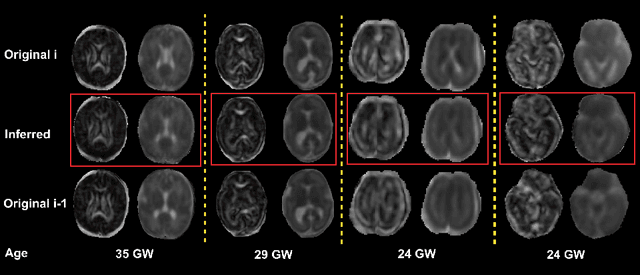

Abstract:Diffusion MRI (dMRI) of the developing brain can provide valuable insights into the white matter development. However, slice thickness in fetal dMRI is typically high (i.e., 3-5 mm) to freeze the in-plane motion, which reduces the sensitivity of the dMRI signal to the underlying anatomy. In this study, we aim at overcoming this problem by using autoencoders to learn unsupervised efficient representations of brain slices in a latent space, using raw dMRI signals and their spherical harmonics (SH) representation. We first learn and quantitatively validate the autoencoders on the developing Human Connectome Project pre-term newborn data, and further test the method on fetal data. Our results show that the autoencoder in the signal domain better synthesized the raw signal. Interestingly, the fractional anisotropy and, to a lesser extent, the mean diffusivity, are best recovered in missing slices by using the autoencoder trained with SH coefficients. A comparison was performed with the same maps reconstructed using an autoencoder trained with raw signals, as well as conventional interpolation methods of raw signals and SH coefficients. From these results, we conclude that the recovery of missing/corrupted slices should be performed in the signal domain if the raw signal is aimed to be recovered, and in the SH domain if diffusion tensor properties (i.e., fractional anisotropy) are targeted. Notably, the trained autoencoders were able to generalize to fetal dMRI data acquired using a much smaller number of diffusion gradients and a lower b-value, where we qualitatively show the consistency of the estimated diffusion tensor maps.